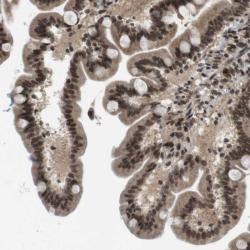

Supportive validation

- Experimental details

- Immunohistochemical staining of human duodenum shows nuclear and cytoplasmic positivity in glandular cells.

- Validation comment

- Staining pattern partly consistent with experimental and/or bioinformatic data.